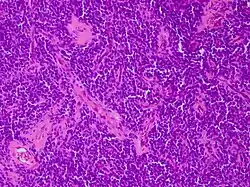

Micrograph of an H&E stained section of a peripheral PNET.

CD99 staining of tissue from peripheral PNET